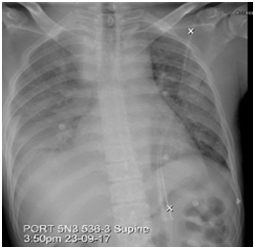

A CT scan of the neck was done due to clinical suspicion of a retropharyngeal abscess, which showed multiple enlarged necrotic lymph nodes on the right side of the neck (Figure 2). His initial management consisted of empiric antibiotics (Amoxicillin + Clavulanic Acid) and regular paracetamol, while the results of further tests were awaited. Subsequently, there was a reduction in the size and tenderness of the cervical lymph nodes, but there were persistent intermittent temperature spikes. Ten days after the initial presentation, he developed an episode of acute confusion with a drop in saturation and abnormal movements. He also complained of a severe headache, but there was no nuchal rigidity. Kernig's and Brudzinski's signs were also negative. Computed Tomography (CT) head, Magnetic Resonance Imaging (MRI) Brain, and electroencephalogram (EEG) were unremarkable. In MRI, there was no evidence of Lupus cerebritis or central nervous system (CNS) vasculitis. Lumbar punctures showed high protein, low sugar, and 22 white blood cells with 92%lymphocytes. Cerebrospinal fluid (CSF) culture and Viral PCR were negative, and hence this followed a pattern of aseptic meningitis. He was empirically treated with acyclovir and meropenem for two days, which were later discontinued. He made a spontaneous recovery from CNS symptoms over the next eight days. Excisional biopsy of the right cervical Level 3 and Level 5 Lymph nodes confirmed a diagnosis of Kikuchi-Fujimoto disease (KFD). Histological analysis showed histiocytic granulomatous infiltration with widespread necrosis of the lymph node extending beyond its capsule into the surrounding fat. There were areas of xanthomatous cells and areas of partial coagulative necrosis with some karyorrhexic debris containing a variety of cells, including histiocytes, plasmacytoid monocytes, some immunoblasts, and some small and large lymphocytes. Immunohistochemistry was also consistent with this diagnosis.

Figure 2 A CT scan of the neck showing multiple enlarged necrotic lymph nodes on the right side of the neck.